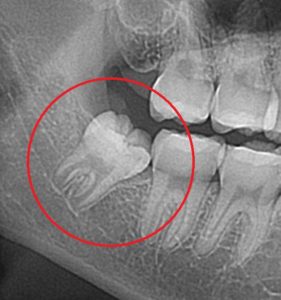

レントゲン写真です。

赤丸の場所に、斜めに生えてきている親知らずがあります。